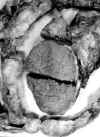

Macroscópicamente observamos una bolsa testicular parcialmente abierta, formada por una túnica vaginal parietal muy engrosada que al corte mostraba una neoformación de aspecto multinodular que afectaba globalmente a toda la túnica, rodeando al testículo sin infiltrarlo (fig. 1). Su consistencia era firme, dura, densa, homogénea, amarillenta oscura (tras la fijación de la pieza) sin poder valorar sus diámetros longitudinal ni transversal y con un espesor parietal máximo de 1,4 cm (fig. 2). El epidídimo estaba replegado y adherido en algunas zonas a la neoformación descrita. La cabeza del epidídimo quedaba libre.

Fig. 1. La proliferación fibrosa de la vaginal es multinodular y difusa con

conservación del parénquima testicular que queda libre.

Fig. 2. Área macroscópica del carácter

nodular fibroso de la figura 1.